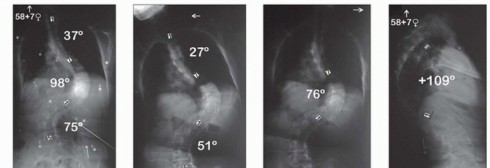

Posterior Osteotomies of the Spine DEFINITION Spinal osteotomies encompass a range of techniques involving re…

Vertebral Column Resection for Severe Rigid Spinal Deformity through an All Posterior Approach DEFINITION Pos…

Hemivertebra Excision DEFINITION A hemivertebra is a congenital anomaly of the spine that forms during the 8t…